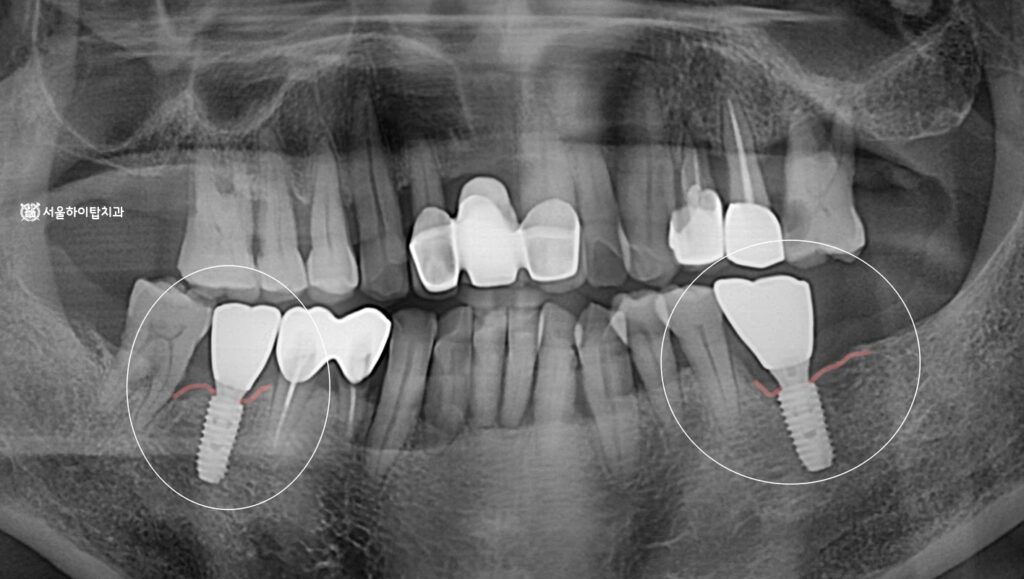

초진 파노라마 엑스레이를 확인해 보면,

앞서 간석오거리 치과 에서 말씀드린

문제들이 모두 확인됩니다.

사진 기준 왼쪽 부위는

오랜 기간 상실된 어금니,

반면 오른쪽 부위는 치주염으로 인해

치조골이 녹아내린 모습이 보입니다.

즉,

1) 장기간 방치된 무치악 부위,

2) 치주염으로 인한 골 소실 부위,

이 두가지 서로 다른 문제를

동시에 가지고 있는 것이죠.